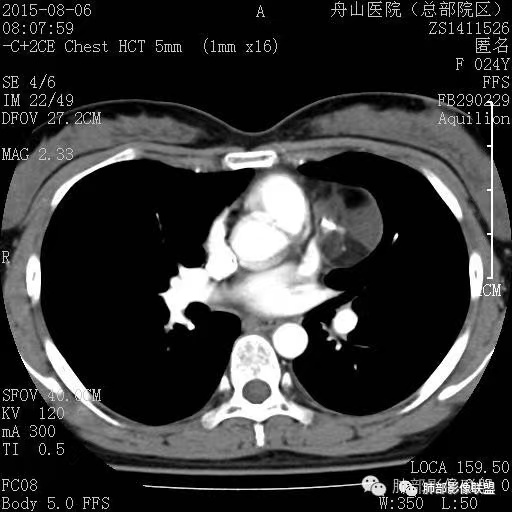

4、绒毛膜癌

纵隔原发性绒毛癌病人几乎为男性,也是高度恶性生殖细胞肿瘤,血、尿β-HCG升高是绒毛膜癌的一个特征,男性乳房发育,影像表现呈分叶状巨大肿块,亦出血坏死,富血供病变,易侵犯血管,所以早期容易出血转移,最常累及的器官为肺。

男性,12岁,绒癌伴双肺转移